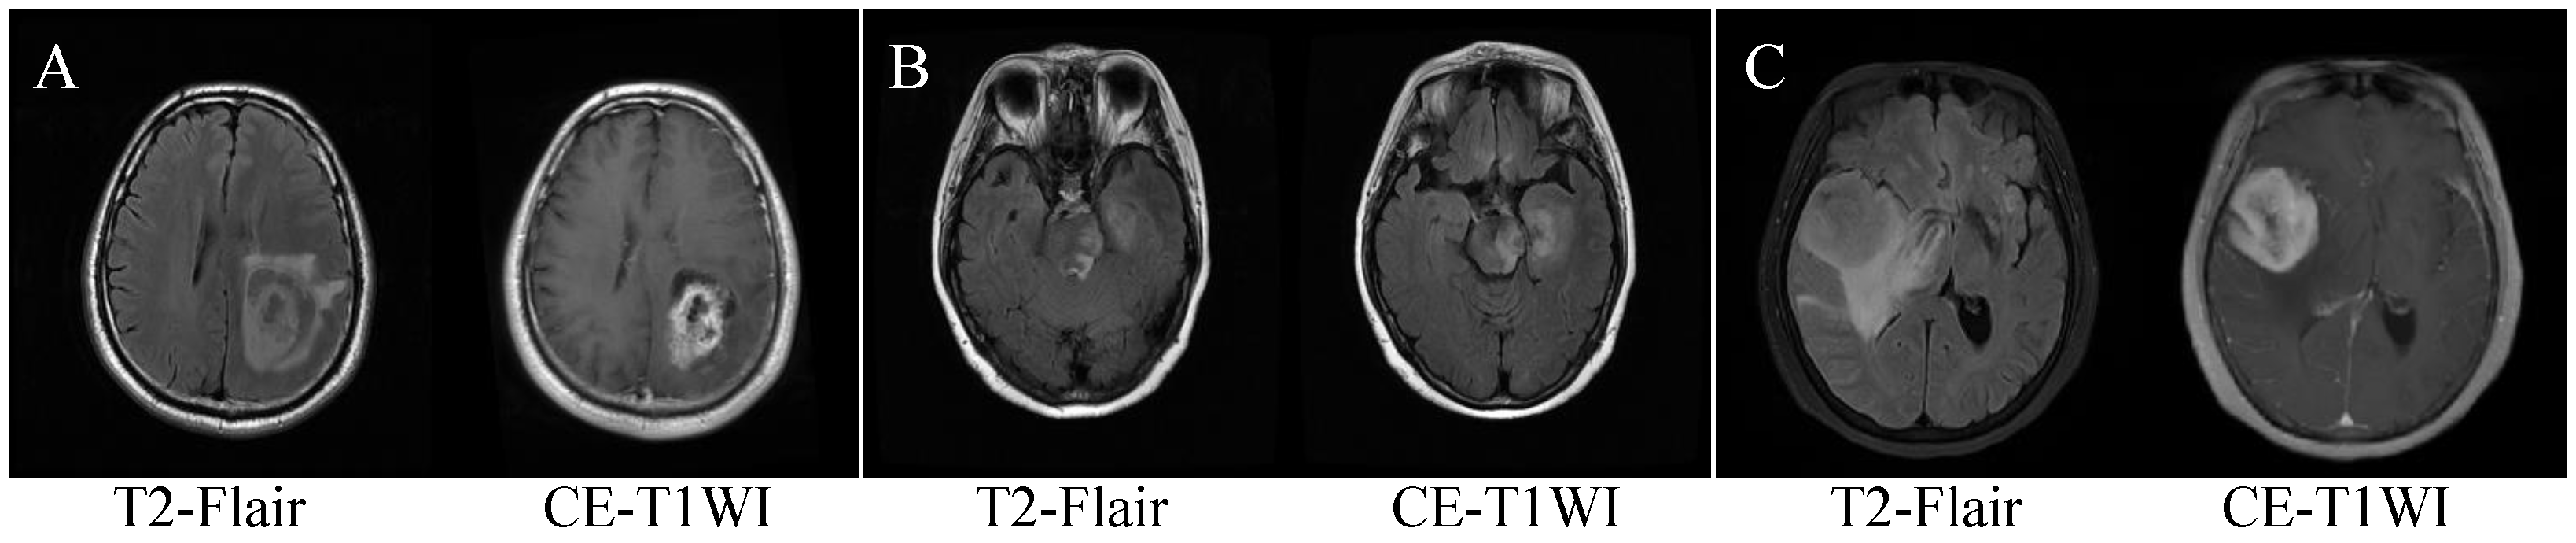

2. Patients

2.1. Patient Enrollment and MRI Scanning Parameters

2.2. Data Preprocessing